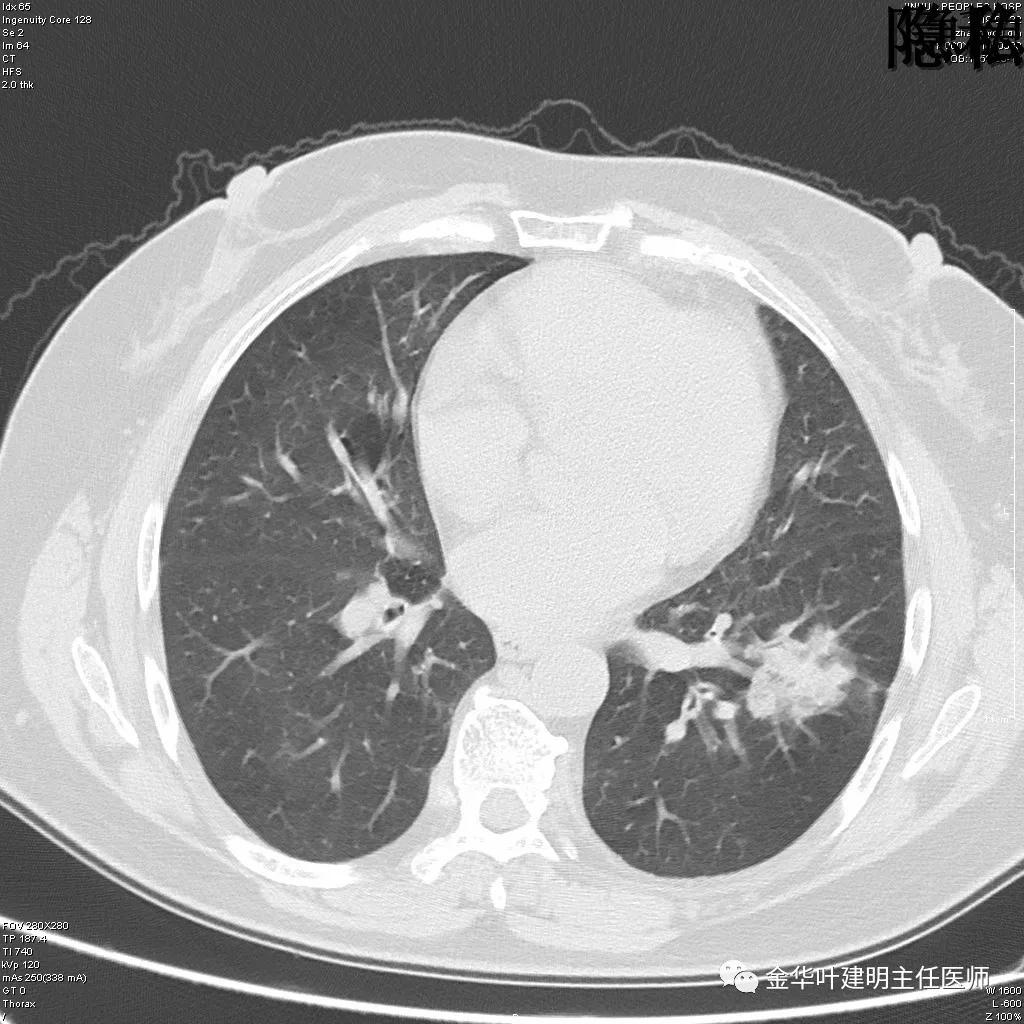

(病例资料2019年)金华的章某,今年60岁,前段时间因为咳嗽,到市区某三甲医院检查,发现她的左肺上叶与左肺下叶都有占位性病变。由于章某有亲戚在我们医院工作,所以在亲戚的指引下,让她来找我。我们予以适当的抗炎治疗,然后复发CT,发现病灶没有任何变化。其中平扫的片子如下:

可见左肺上叶有一占位,是空腔性的,其内有实性密度填充,是比较典型的肺曲菌病的表现,但病灶有点大,长径大于3-4厘米许。

可见左肺下叶比较靠中央的部位也有一病灶,是混合磨玻璃影,偏实性,瘤肺边界清楚,是较为典型的肺癌表现。进一步的靶扫描图像如下: